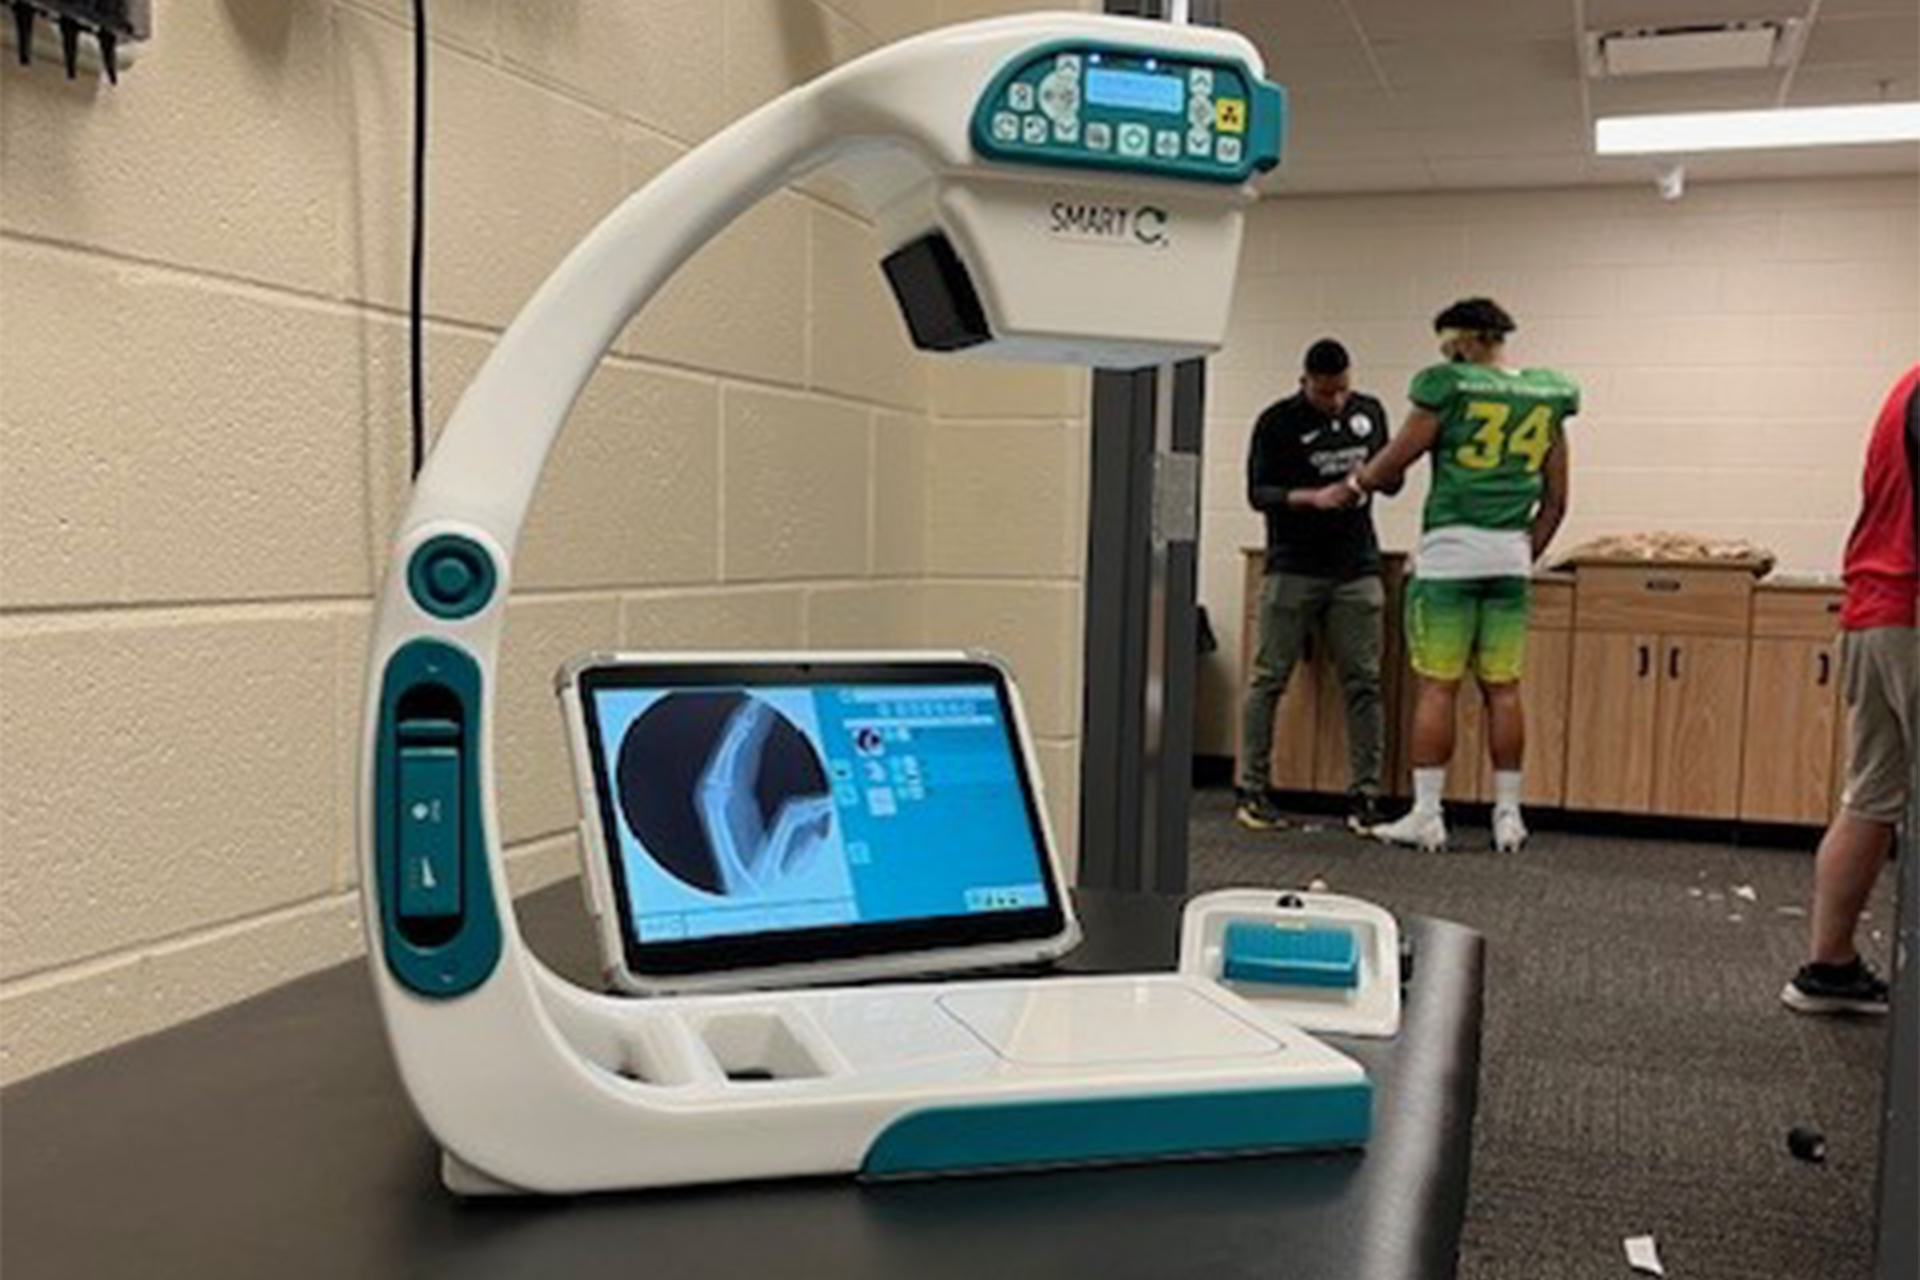

In sports medicine, the ability to quickly and accurately diagnose injuries is crucial for effective treatment and recovery. SMART-C® utilizes fluoroscopy to provide real-time imaging at the point-of-care, setting it apart from traditional X-ray systems that only provide static radiography.

This article delves into five common sports injuries, providing detailed clinical insights and explaining why the SMART-C® is the superior option for point-of-care imaging.

The SMART-C’s fluoroscopic imaging delivers high-resolution, real-time visualization of fractures, which is essential for assessing their morphology, displacement, and involvement of adjacent structures. Unlike traditional x-ray systems that provide only a static image, the SMART-C® allows for a dynamic assessment, capturing images from multiple angles to provide a comprehensive view. For example, in a spiral fracture, the SMART-C can reveal many aspects of the fracture by assessing shortening, angulation, malrotation, and translation, aiding in precise reduction and surgical planning. The ability to have SMART-C® at the point-of-care for immediate on-site imaging reduces delays in diagnosis and treatment, which is critical for optimal patient-centric recovery.

SMART-C® offers detailed fluoroscopic images that accurately depict the spatial relationship of dislocated bones and any associated fractures. Its portability allows for immediate, on-site imaging, which is crucial for prompt reduction procedures. With the SMART-C®, real-time imaging can guide the reduction process and confirm successful relocation, reducing pain and preventing further injury.

The SMART-C®’s fluoroscopic imaging is highly sensitive in detecting stress fractures. Traditional x-rays often miss these subtle changes due to their static nature. The SMART-C® provides dynamic, real-time imaging, allowing for a more detailed and comprehensive assessment. This capability enables early diagnosis and timely intervention, such as rest and activity modification, preventing further damage and facilitating quicker recovery.

SMART-C® provides high-definition fluoroscopic images crucial for evaluating intricate fractures such as scaphoid or distal radius fractures. Unlike traditional x-rays that offer a single static view, the SMART-C’s ability to perform multiplanar imaging ensures a thorough assessment of fracture patterns and associated soft tissue injuries. For example, in scaphoid fractures, the super fine resolution (99-micron pixel size) of SMART-C® enables physicians to detect subtle fractures that traditional x-rays might miss, allowing for early and appropriate treatment to prevent non-union and other long-term complications.

The SMART-C’s fluoroscopy provides dynamic, high-resolution images of the ankle joint, enabling detailed assessment of fracture lines, displacement, and joint congruency. Traditional x-ray systems provide static images, which can be limiting. The SMART-C’s portability ensures immediate on-site imaging, crucial for early intervention. In trimalleolar fractures, for example, the SMART-C can guide reduction and stabilization procedures, ensuring proper alignment and minimizing complications.

The SMART-C® revolutionizes sports medicine by offering immediate, high-quality fluoroscopic imaging essential for diagnosing and managing osseous injuries. Its portability, ease of use, and advanced imaging capabilities make it a superior option compared to traditional x-ray systems that provide only static radiography.

The SMART-C® revolutionizes sports medicine by offering immediate, high-quality fluoroscopic imaging essential for diagnosing and managing osseous injuries. Its portability, ease of use, and advanced imaging capabilities make it a superior option compared to traditional x-ray systems that provide only static radiography.

Whether physicians are using the SMART-C® and tablet at the point-of-care or mounted on the support stand in a medical room, they have the flexibility to acquire sharp motion images at the exact angle needed, to properly treat their athletes. By facilitating prompt and precise assessment of bone fractures, dislocations, stress fractures, wrist and hand injuries, and ankle fractures, the SMART-C® significantly enhances the management and recovery of sports-related injuries.

The SMART-C® revolutionizes sports medicine by offering immediate, high-quality fluoroscopic imaging essential for diagnosing and managing osseous injuries. Its portability, ease of use, and advanced imaging capabilities make it a superior option compared to traditional x-ray systems that provide only static radiography.

The SMART-C® revolutionizes sports medicine by offering immediate, high-quality fluoroscopic imaging essential for diagnosing and managing osseous injuries. Its portability, ease of use, and advanced imaging capabilities make it a superior option compared to traditional x-ray systems that provide only static radiography.